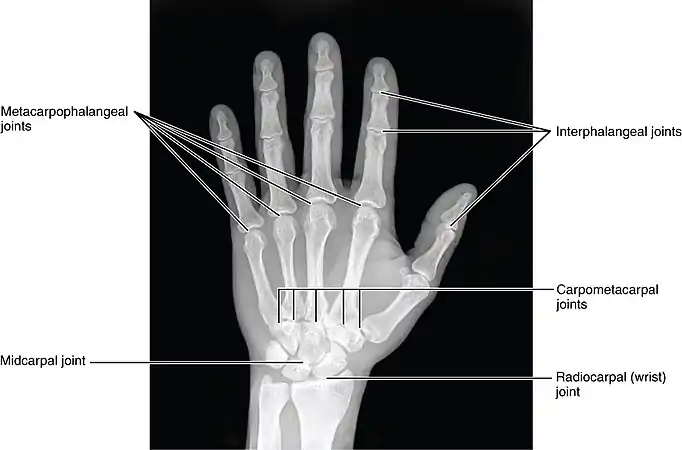

The intercarpal joints (joints of the carpal bones of the wrist) can be subdivided into three sets of joints (also called articulations): Those of the proximal row of carpal bones, those of the distal row of carpal bones, and those of the two rows with each other.

The bones in each carpal row interlock with each other and each row can therefore be considered a single joint. In the proximal row a limited degree of mobility is possible, but the bones of the distal row are connected to each other and to the metacarpal bones by strong ligaments that make this row and the metacarpus a functional entity. [1]

Midcarpal

- See Midcarpal joint

These four surfaces form two joints: (1) a proximal, the wrist-joint proper; and (2) a distal, the mid-carpal joint.

Mid-carpal joint